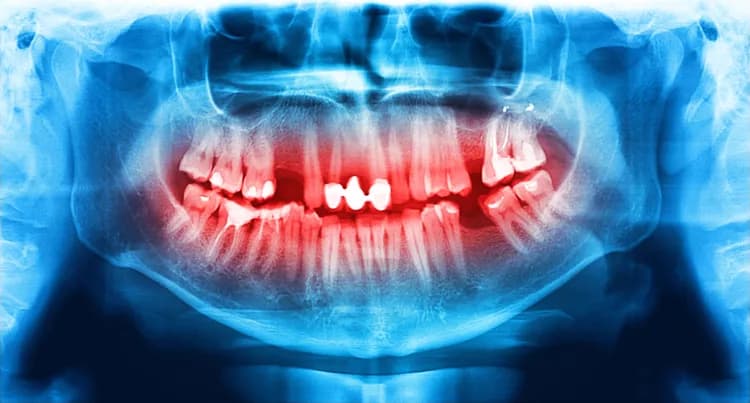

A study published in the Journal of Oral Rehabilitation by a group of scientists in Israel states that for people suffering from social anxiety disorder, the risk of bruxism (teeth clenching, grinding) and oral parafunctional hyperactivity (nail biting, pencil biting, gum chewing, small jaw movements without teeth contact, etc.) is elevated. This could lead to tooth wear, jaw pain, and fracture.

Social anxiety, along with selective serotonin reuptake inhibitors (SSRIs) prescribed for depression, is considered an aggravating factor for teeth grinding or bruxism. There are two types of bruxism: